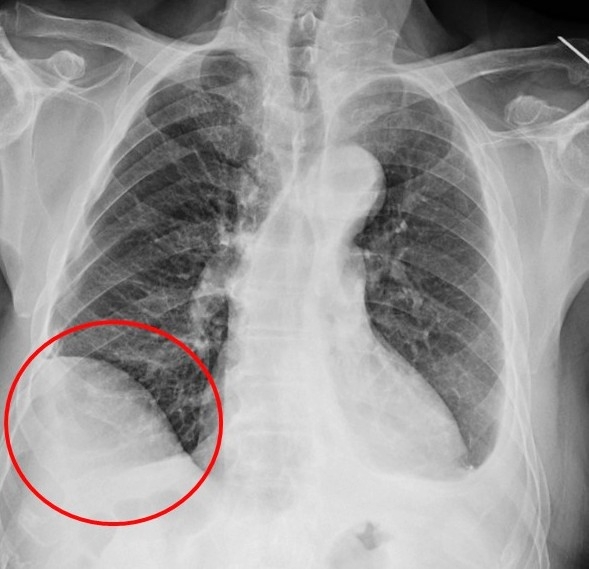

▲電腦斷層顯示病人的肺結節位於橫膈膜正後方。(圖╱仁愛長庚醫院提供)

▲病人創傷後橫膈膜沾黏,右側橫膈膜明顯升高。(圖╱仁愛長庚醫院提供)